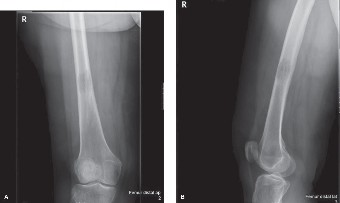

A 60-year-old female with a history of breast cancer treated 5 years ago with mastectomy, chemotherapy, and r…